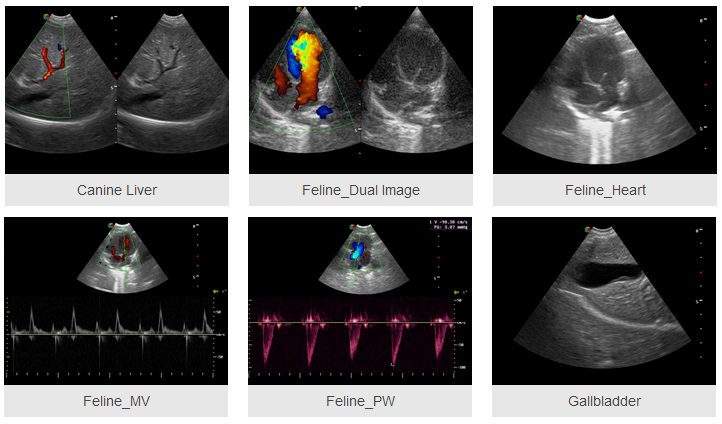

Color Doppler Ultrasound

The S2V, a newly-released veterinary color Doppler ultrasound system, is built on a new platform and architecture in a compact design that is ideal for taking excelle

nt performance no matter in the consult room or on a equine yard.

To meet the growing needs of today's veterinarians, the S2V is equipped with a dedicated veterinary fully configured software package featuring professional measurement packages and reports, specialized application icons and body marks.

Due to the wide range of dedicated veterinary special purpose transducers with frequencies ranging from 2 to 15 Mhz, the S2V will provide you with optimal coverage in all fields of various animal veterinaries.

Powerful veterinary measurement and calculation software package: early pregnancy diagnosis, cardiac diagnosis, general abdominal diagnosis, reproductive evaluation

Professional veterinary high density linear array for endocavity reproductive and superficial application

Phased array and micro-convex transducers for abdominal and cardiac application